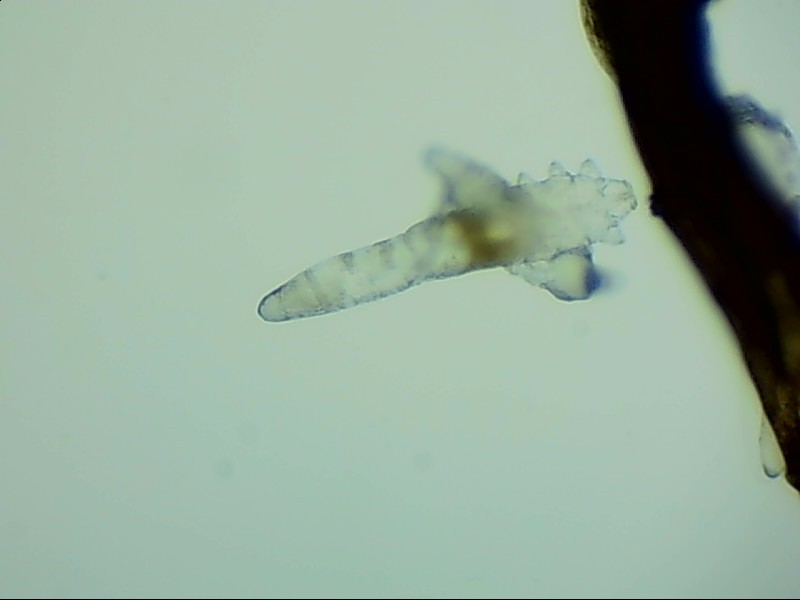

蠕形螨:

人體上寄生著兩種蠕形螨,分別是毛囊蠕形螨和皮脂蠕形螨,它們以睫毛囊上皮細(xì)胞、腺體內(nèi)脂質(zhì)為食物,因此主要寄生在面部、眼睛、頭皮等地方,其中寄生在眼睛里的蠕形螨主要活動(dòng)在睫毛毛囊、睫毛皮脂腺,以及瞼板腺里。

蠕形螨完全長(zhǎng)大也只有0.1-0.2毫米,因此肉眼難以看到它們,只有在電子顯微鏡下我們才能看到睫毛根部的一只只蠕形螨。這些螨蟲每天都很活躍,且繁殖速度極快,完成一代生活史僅需大概15天。

螨蟲鏡檢主要是通過(guò)顯微鏡觀察,它能無(wú)死角放大你的睫毛,讓螨蟲無(wú)處可躲。

在檢查的時(shí)候,醫(yī)生要在每個(gè)眼瞼上拔出幾根比較典型的睫毛,然后放在光學(xué)顯微鏡下,尋找有沒(méi)有螨蟲,同時(shí)觀察螨蟲的數(shù)量多少。